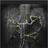

Radiograph #2

Celiac Artery

Identify: Celiac trunk, common hepatic artery, proper hepatic artery, gastroduodenal artery, superior anterior/posterior pancreaticoduodenal artery, right gastoepiploic artery, left gastroepiploic artery, splenic artery, short gastric artery.